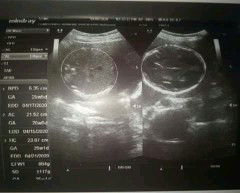

Momshh done na po sa ultrasound suhe po sya kase 6months palang naman po . Pero iikot parin naman daw sabi ni doC. .. my naisip na po akong pangalan sa kanya kaso ayaw naman ng papa nya pati ng tiyahin ko pambabae daw kase , ang naisip ko "SEAN MEI" kayo na po humusga . Kunq pangit po give me some name sa bandang dulo , Ok naman yung SEAN eh yung MEI daw pang girl ^^ thanks po :)